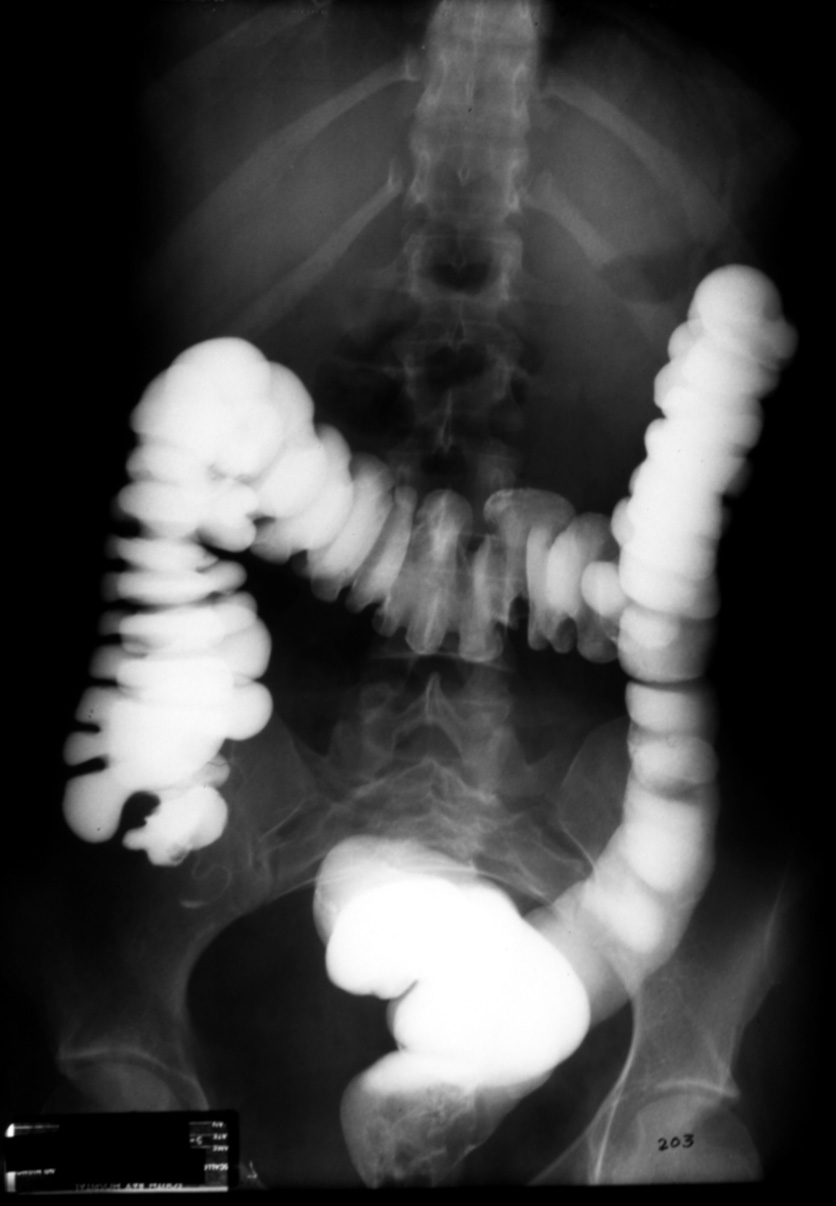

MS I 203 - Normal Barium Enema (BE)